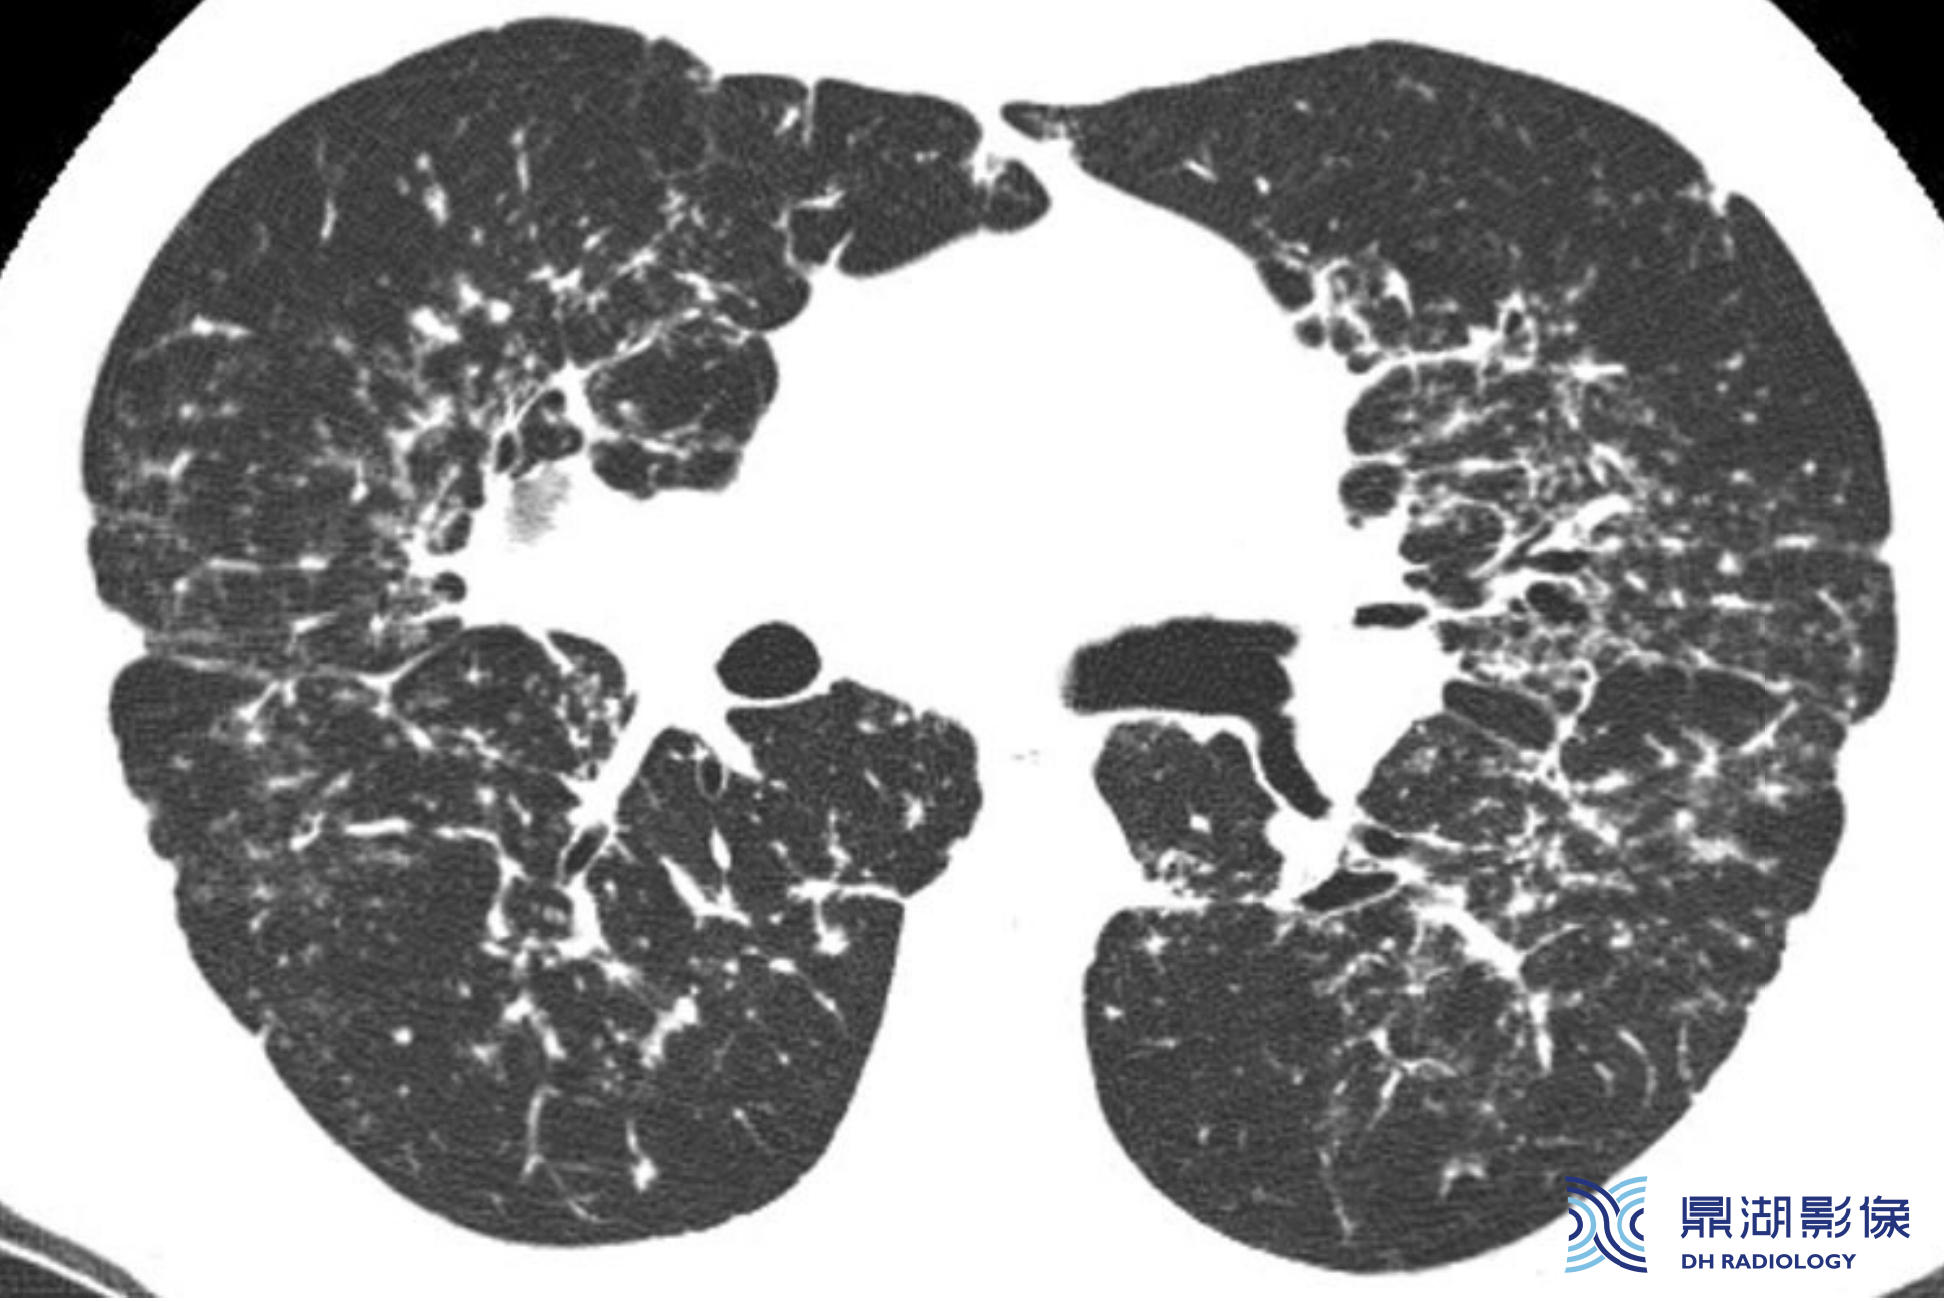

(五)纤维化

约20%结节病患者出现肺纤维化,提示预后不良。纤维化通常分布于上叶、肺门及支气管血管周围。不规则的网状影常见,部分患者可见纤维化团块,且常伴有牵拉性支气管扩张和不规则的支气管充气征。也可存在蜂窝征。但纤维化的总体分布不同于特发性肺纤维化(IPF)。IPF的纤维化通常分布在肺基底部和外周。

76e403bbb3770d689416a6529ed6e81d.png

结节病伴纤维化的典型表现。不规则的网状影主要分布在上叶、肺门旁和支气管血管周围,也可见于叶间裂和胸膜下。